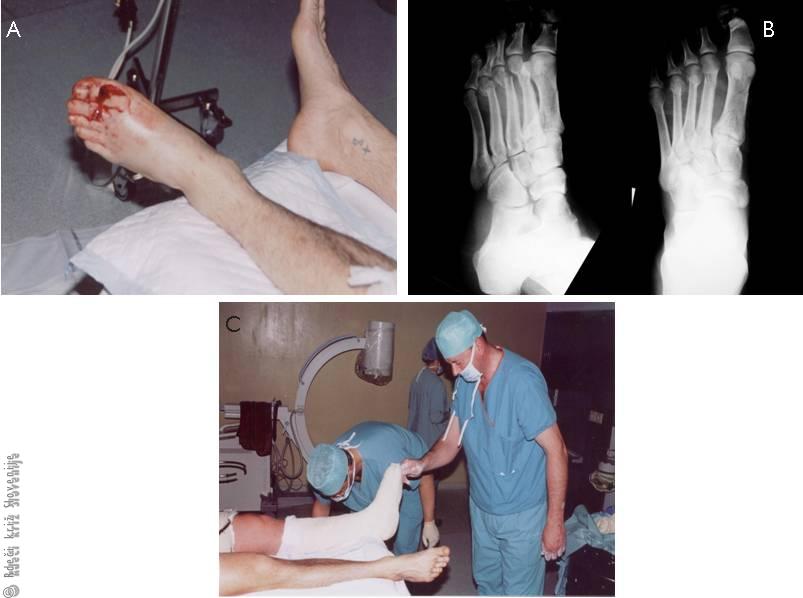

Slika 9

A – Izgled poškodovanega stopala.

B – RTG slika zlomov stopalnic.

C – Zamavčenje stopala po naravnavi zlomov.